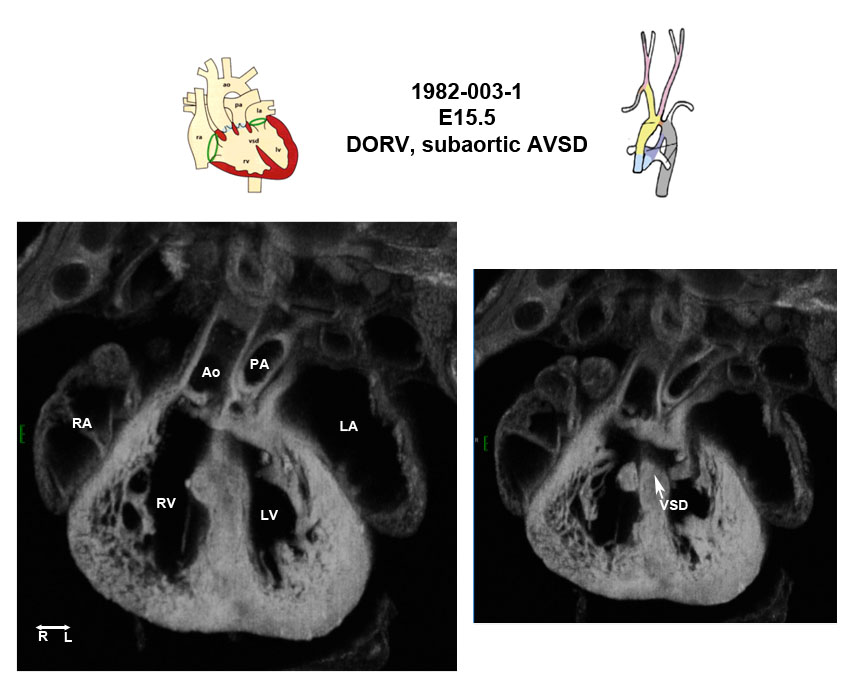

Caption EFIC Summary

Copyright This image is from the Laboratory of Dr. Cecilia Lo, a member of the Cardiovascular Development Consortium (CvDC), Bench to Bassinet (B2B) program of the National Heart Lung and Blood Institute (NHLBI), and is displayed with the permission of the authors. J:175213

Zbtb14b2b1982Clo zinc finger and BTB domain containing 14; Bench to Bassinet Program (B2B/CVDC) mutation 1982, Cecilia Lo

Zbtb14b2b1982Clo/Zbtb14b2b1982Clo C57BL/6J-Zbtb14b2b1982Clo